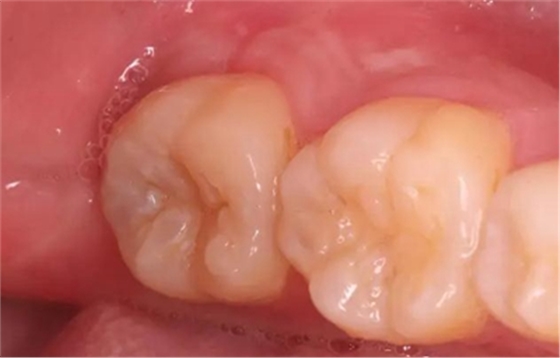

圖1 術(shù)前口內(nèi)照,37合面窩溝形態(tài)完好,

遠(yuǎn)中牙體輕度“墨浸樣”變色,探及遠(yuǎn)中齦下深齲洞